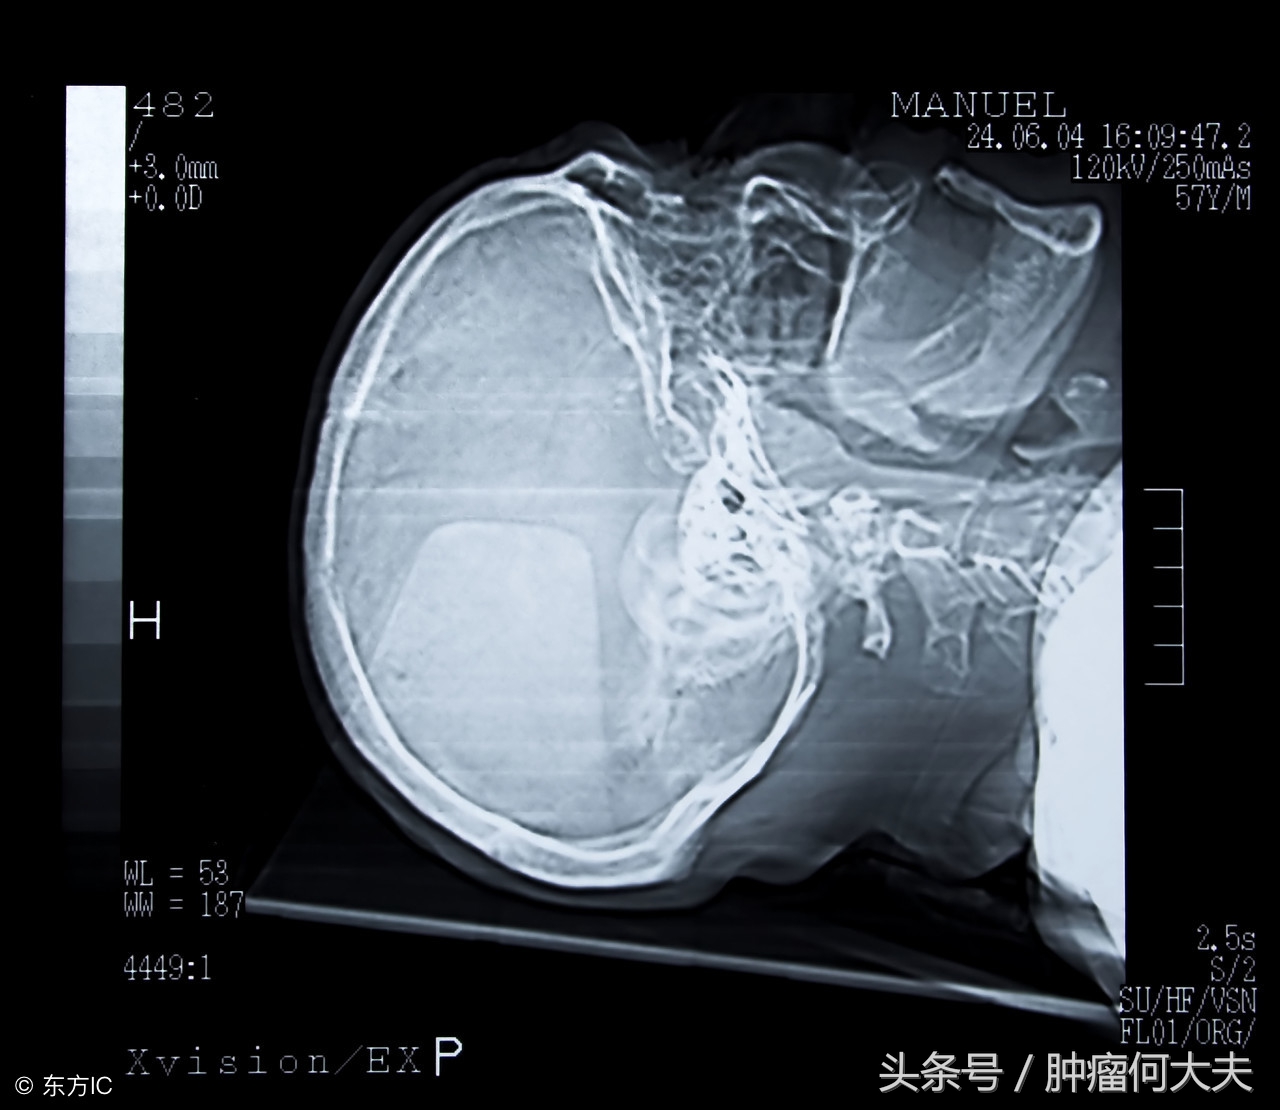

怀疑脑膜瘤要做哪些检查? 头颅CT及MRI增强检查:能提供肿瘤大小、部位、能否手术等重要信息。脑膜MRI特点是显示肿瘤均一强化,有硬膜尾征,有皮质扣压征,有假包膜形成,瘤周水肿,骨质破坏;脑血管造影检查:可见肿瘤染色,供血动脉增粗,颈动脉血循环增快;PET-CT检查:对了解病变浸润范围及有无术后残留和复发有重要的参考价值。患者有上述临床表现并有影像学表现之一者即可临床诊断脑膜瘤。确诊及病理分类依靠术后病理组织学检查。